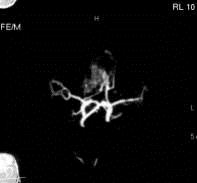

问题 病历摘要:??患者男性,56岁,因右侧视力下降伴视野缺损2个月来院就诊,诉头痛,无明显头晕,无视物重影,无恶心呕吐,无肢体抽搐,无肢体乏力,胃纳佳,大小便正常,既往史无特殊,入院检查:神志清楚,言语清楚,体毛分布正常,左侧视力4.6,右侧视力4.0,粗侧右颞侧视野缺损,左侧正常,颈软,四肢肌张力正常,肌力正常,病理征(-)。 巨型动脉瘤根据瘤腔内血栓的多少如何正确分型?

选项 A.小部分血栓形成 B.大部分血栓形成 C.部分血栓形成 D.不完全血栓形成 E.完全血栓形成 F.无血栓形成

答案 CEF